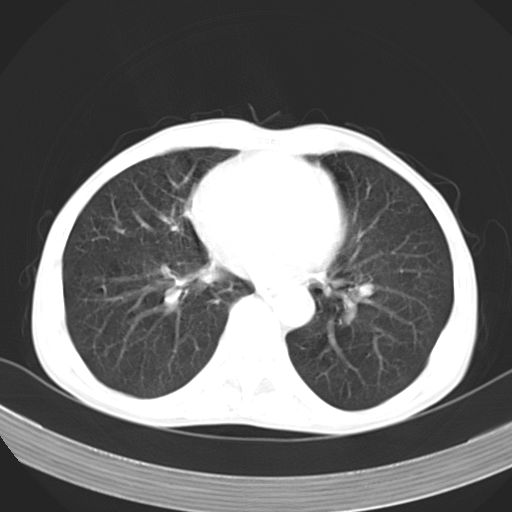

以下是引用苯小孩在2007-5-24 12:47:00的发言:[br]右侧肺门处不均匀密度软组织块影,远端肺组织见斑片模糊影,纵隔内淋巴结明显肿大,边界不清.<纵隔窗第12层面支气管内似见软组织结节>[br]考虑:1、右侧中央性肺癌并阻塞性肺炎并纵隔淋巴结转移可能性大.建议强化或纤支镜进一步检查.[br]2、隆突下淋巴结肿大/食道病变?请做鉴别检查.

以下是引用jw-830在2007-5-24 15:24:00的发言:[br][br] [br] 考虑右肺中央型肺癌并阻塞性炎症,右肺门及纵隔淋巴结转移。 [br] [br][br]